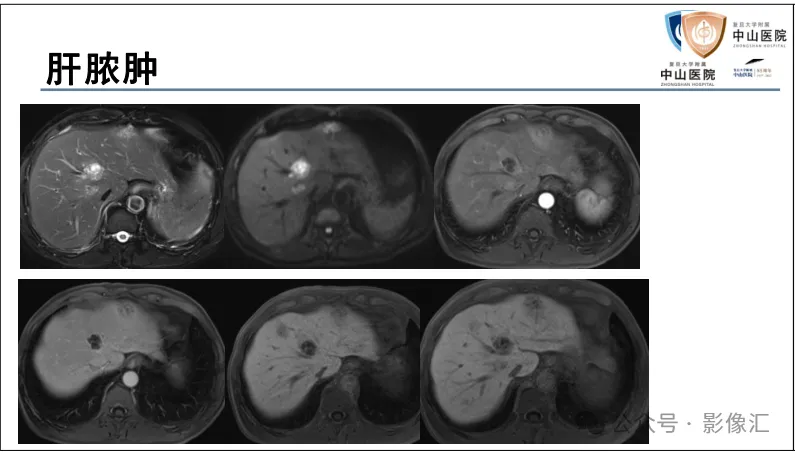

>【精品课件】如何正确判读肝胆特异性对比剂增强图像?

肝胆特异性对比剂增强肝胆图像判读方法与策略,课件来源于网络,作者复旦大学附属中山医院放射科饶圣祥教授。